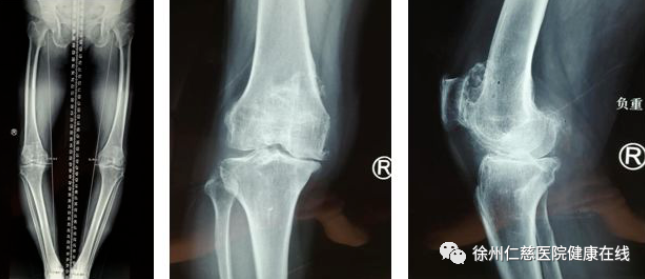

在betway在线登陆关节外科,医生详细给高老太检查后,发现其因为病史较长,双膝关节变形较为严重,已发展为晚期的骨性关节炎,只能行膝关节置换手术。因为右膝关节疼痛更厉害,关节外科专家团队经过研究讨论,决定为高老太先进行导航下的右侧人工膝关节置换术。

长久以来,下肢力线一直被视作膝关节置换术的“生命线”,术中力线位置放置的准确与否极大程度上决定了患者术后的功能恢复,甚至假体的寿命。然而,传统手术中这一“生命线”的确定通过一个简单的导向杆定位完成,非常依赖于术者的经验判断及患者的解剖特征,术后力线的可重复性欠佳,尤其在面临关节外畸形等复杂患者时精确性更难以保障。计算机导航技术的出现为这一困境提供了解决方案。